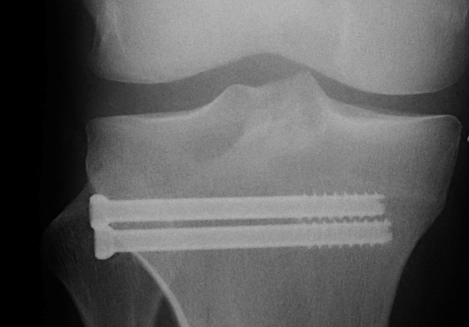

Technique

- elevate and restore joint line

- compress with bone reduction forcep

- stabilise joint line with 2 x 6.5 mm cannulated partially threaded screws

- check fluoroscopy

- restore alignment via application anatomically contoured 4.5 mm locking plate

- often use BG or substitutes under depression fractures laterally